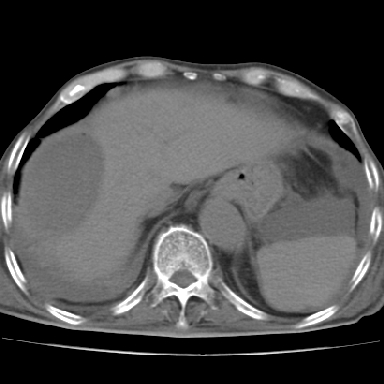

以下是引用qian在2006-12-4 19:11:00的发言:[br]胸腔和腹腔内均见有液性影,肝上极包膜下有一较大椭圆形低密度影,密度均匀,边缘清晰,结合病史考虑术后肝脓肿并胸腹腔积液。

以下是引用chry3在2006-12-4 21:05:00的发言:[br]应该往上扫几层,我考虑膈下脓肿。[br]大家考虑:胃部手术怎会造成肝内脓肿,隔下脓肿到是会造成的

以下是引用dyqct在2006-12-4 19:54:00的发言:[br]考虑:1、肝包膜下脓肿;[br] 2、少量腹水;[br] 3、右侧少量胸膜腔积液。